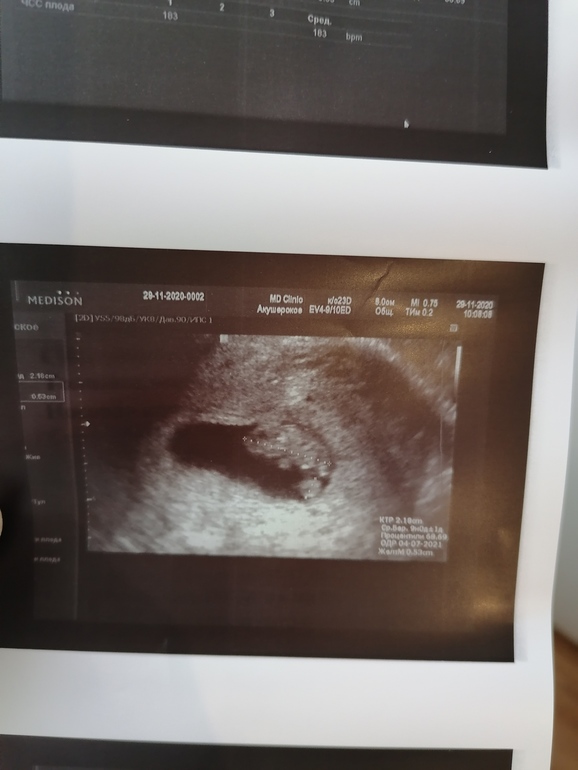

8 недель и 5 дней УЗИ 💙💙💙

Малышочек уже 22мм, что соответствует 9 неделям и значит опережает на 2 дня🥰. Сердечко 182 удара. Уже ручки и ножки видны, такой упитанный малыш, не зря колобочек прозвала его🙈🥰. Тонусов и отслоек ттттт нет.

Ну и мой сладкий колобок🥰🥰🥰.